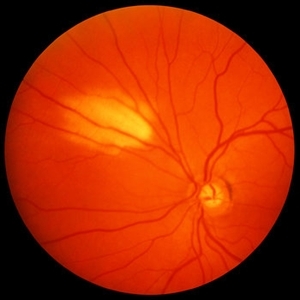

Myelinated Nerve Fibre (MNF)

Sep 12 2023 by Ben Serar

Fundus photograph of RE showing Myelinated Nerve Fibre along superior disc margin

Condition/keywords: MNF, myelinated nerve fiber